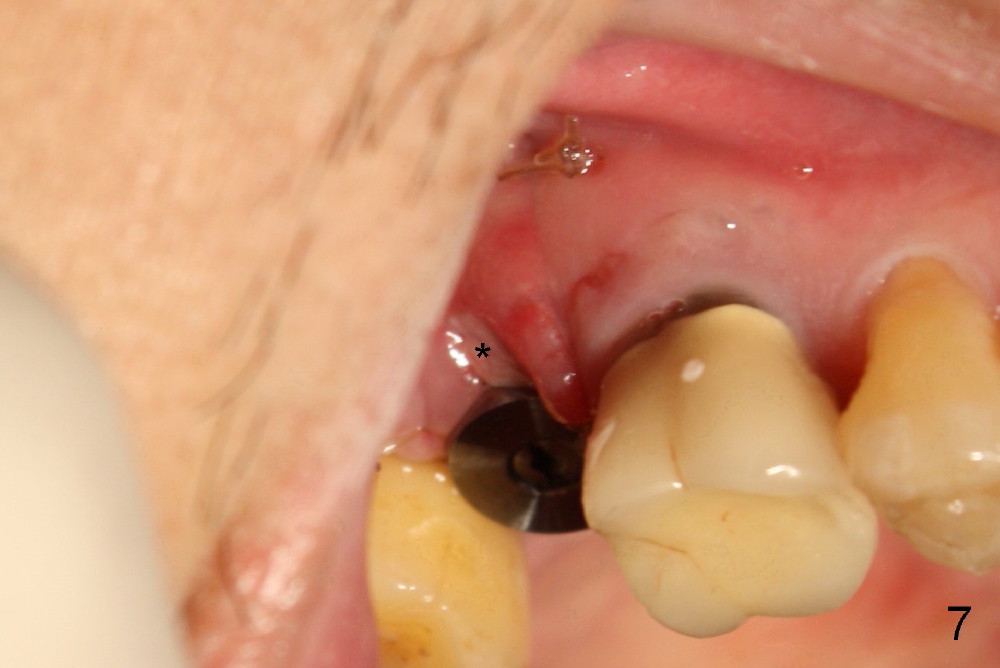

The 60-year-old man is a bruxer. All of the three upper right molars are nonsalvageable (Fig.1). Since #2 is symptomatic, it is planned to be extracted and restored first. As expected, there is severe alveolar destruction (single large socket), while the base bone is solid. A series of tapered osteotomes (2-5 mm) are used to create osteotomy in the base bone (gaining 4 mm into new bone), followed by 4.5x20 mm tap at the depth of 17 mm from the gingival margin (Fig.2). Then the depth is adjusted to 14 mm; the bone expansion and osteotomy continue until using 7 mm tap with good binding to the bone (Fig.3). A 7x14 mm implant is placed with insertion torque more than 60 Ncm (Fig.4). No bone graft is used for sinus lift considering sinus membrane perforation. The buccal flap is raised to reveal bony defect, which is covered by Osteogen (a synthetic bone graft) and then collagen membrane (Fig.6 *). Five days postop, the membrane undergoes a type of transformation (Fig.7 *) leading to a gingival tissue (Fig.8 *, 18 days postop). By 3 months, the gingiva has normal appearance (Fig.9), while the implant seems to be osteointegrated (Fig.10). Once the infected source is removed, our body has potential to regenerate.